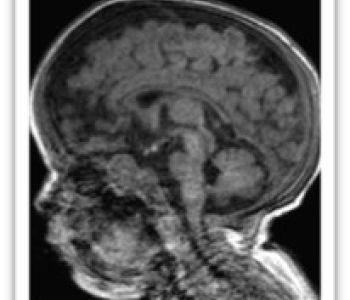

Recién nacido de 35+3 semanas, segundo gemelo de una gestación bicorial-biamniótica que desarrolla en el período fetal un cuadro de crecimiento intrauterino retardado y prenatalmente se detecta una comunicación interventricular, una arteria subclavia derecha aberrante, una arteria umbilical única y una agenesia de ductus venoso.